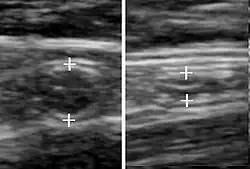

Abdominal ultrasonography, preferably with doppler sonography, is useful to detect appendicitis, especially in children. Ultrasound can show the free fluid collection in the right iliac fossa, along with a visible appendix with increased blood flow when using color Doppler, and noncompressibility of the appendix, as it is essentially a walled-off abscess. Other secondary sonographic signs of acute appendicitis include the presence of echogenic mesenteric fat surrounding the appendix and the acoustic shadowing of an appendicolith.[59] In some cases (approximately 5%),[60] ultrasonography of the iliac fossa does not reveal any abnormalities despite the presence of appendicitis. This false-negative finding is especially true of early appendicitis before the appendix has become significantly distended. Also, false-negative findings are more common in adults where larger amounts of fat and bowel gas make visualizing the appendix technically difficult. Despite these limitations, sonographic imaging with experienced hands can often distinguish between appendicitis and other diseases with similar symptoms. Some of these conditions include inflammation of lymph nodes near the appendix or pain originating from other pelvic organs such as the ovaries or Fallopian tubes. Ultrasounds may be either done by the radiology department or by the emergency physician.[61]

- Ultrasound showing appendicitis and an appendicolith.[62]

- Ultrasound of a normal appendix for comparison.

- A normal appendix without and with compression. Absence of compressibility indicates appendicitis.[59]